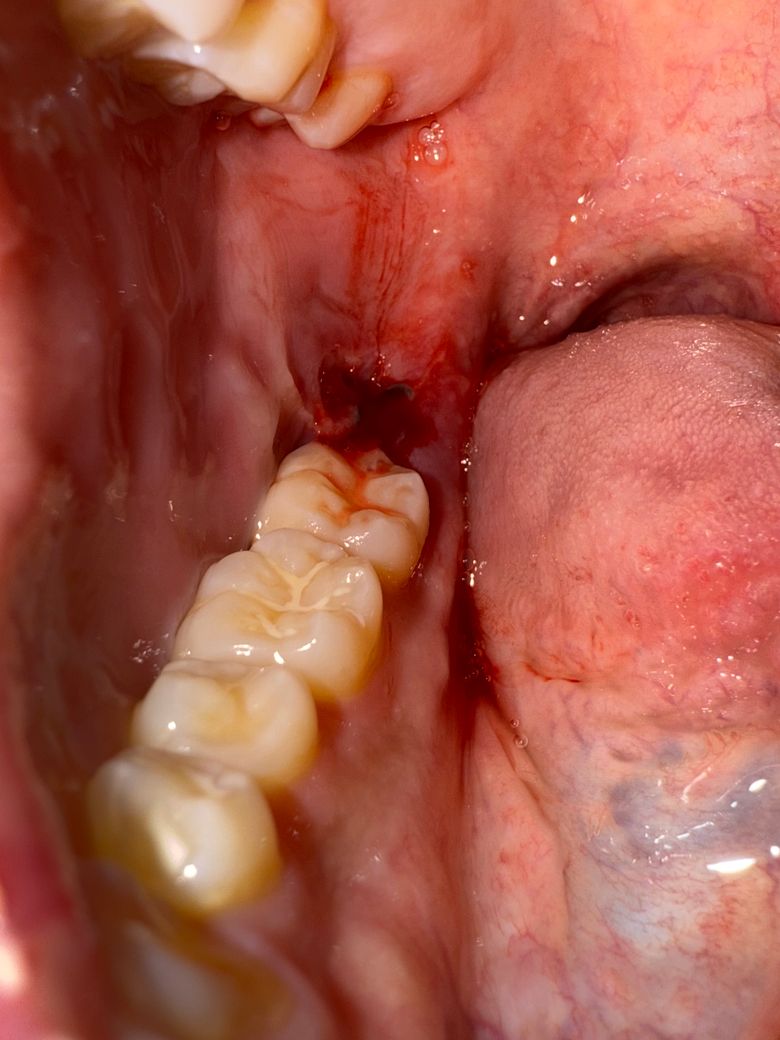

사랑니 발치 4일차인데 피가는데 왜그럴까요…?

운전하고 있었는데 갑자기 입안에서 피맛이 느껴져서 잠깐 정차 후에 보니까 피가 나고 있네요… 2,3일차에는 안났는데 갑자기 4일차에 왜나는 걸까요…그러면서 잇몸 부엇던 붓기가 빠진거 같은 느낌이네요…

사랑니 뽑은 후 피가 멈추었다가 자극이 가면 다시 피가 스며 나오는 경우가 종종 있습니다. 그냥두면 됩니다.

사랑니 발치를 하고나서 피가 계속 난다면 치과에 가셔서 소독을 받으시고 염증이 잇는지 체크를 받아보시는게 좋을것같습니다.

발치 후 약간의 출혈은 일주일까지도 있을 수 있습니다 출혈이 흐를정도라면 거즈로 압박지혈해주세요

사랑니를 발치하고 해당부위에 자극이 가해지게 되면 출혈이 될수 있습니다.

출혈이 된다면 해당부위에 거즈를 물고 있는것이 좋습니다.

출혈이 되어도 침을 뱉거나 삼키지 않고 머금고 있는것이 좋습니다